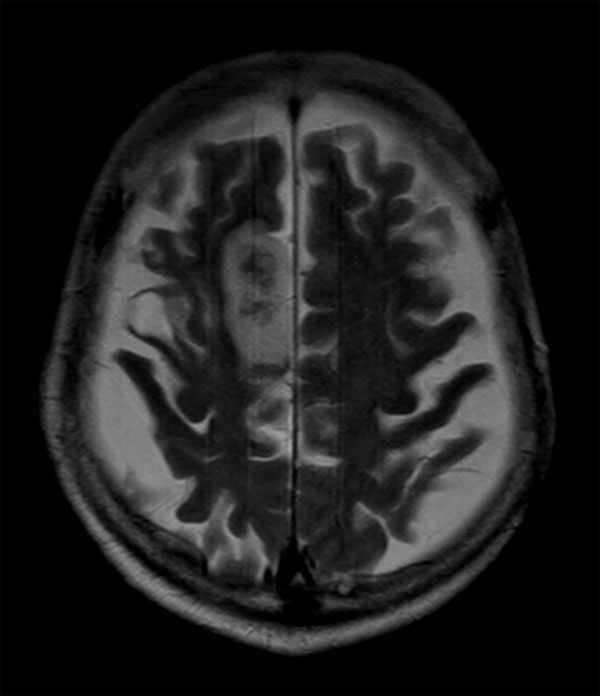

Acute stroke. Patient was brought to the first aid and directly transferred to the MRI unit. Axial studies were performed to get an overview of the stroke. Total study time is 9 minutes.

Axial T2w TSE